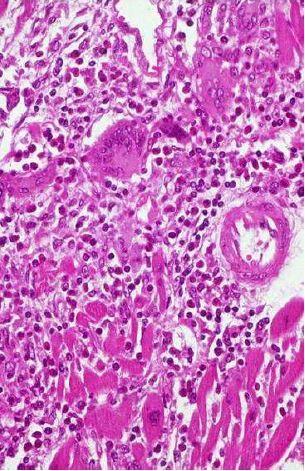

BQ SLIDE!

What is this lesion in the heart?

A

Rheumatic Heart Disease

Picture is showing the characteristic Aschoff nodule composed of Anitschkow cells (seen here)